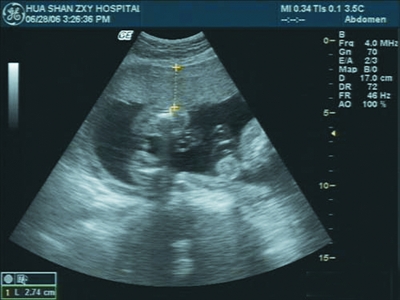

孕妇正在做孕期B超检查。(资料图片)

专家称:二维超声检查已能够对腹中胎儿进行系统筛查。(资料图片)